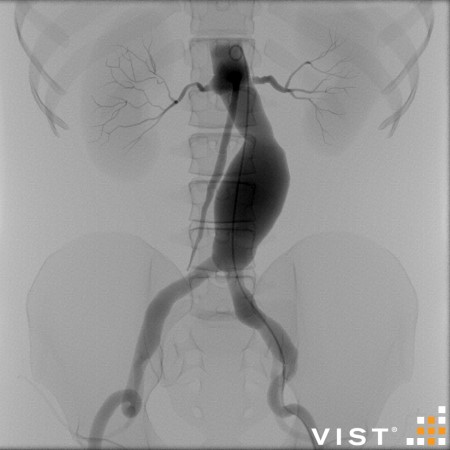

Simuladores Endovanculares.

módulos内血管分发

Aquíhayuna listademódulosundonibles concatibles con el simulador vist g5(Versiónforporidenteyy lab,没有兼容的孔血管y vist灯)。Esta listaestántancoreeevolución,没有Dude en advertarla promicy ... los dutallesestándisponibles haciendo clic en eltítulodelmódulo(网站蒙黛尔,enInglés)